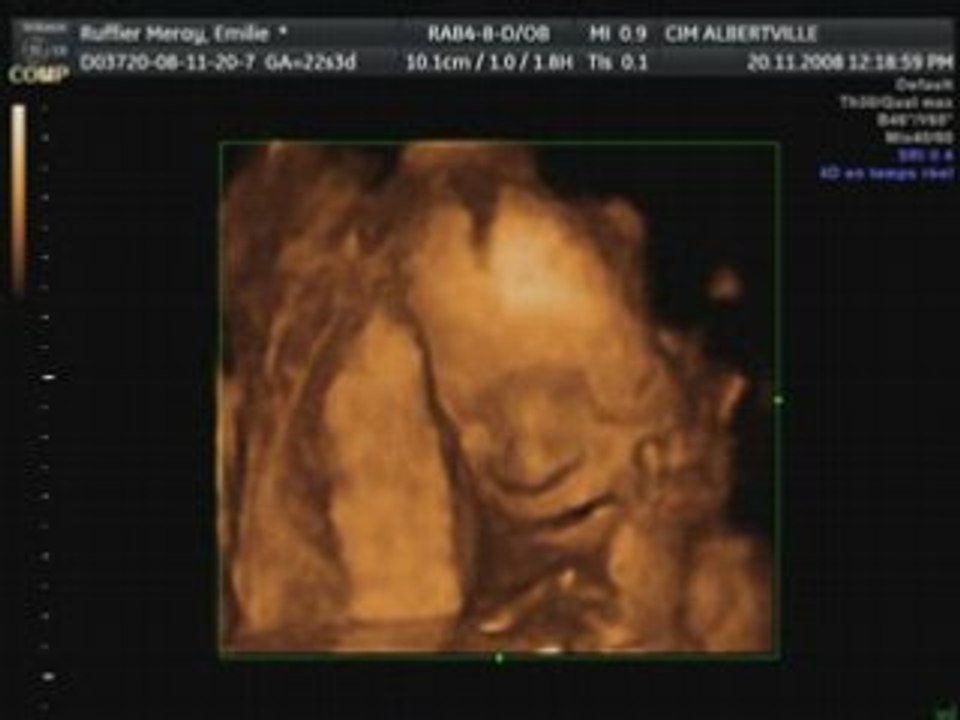

_emilie_